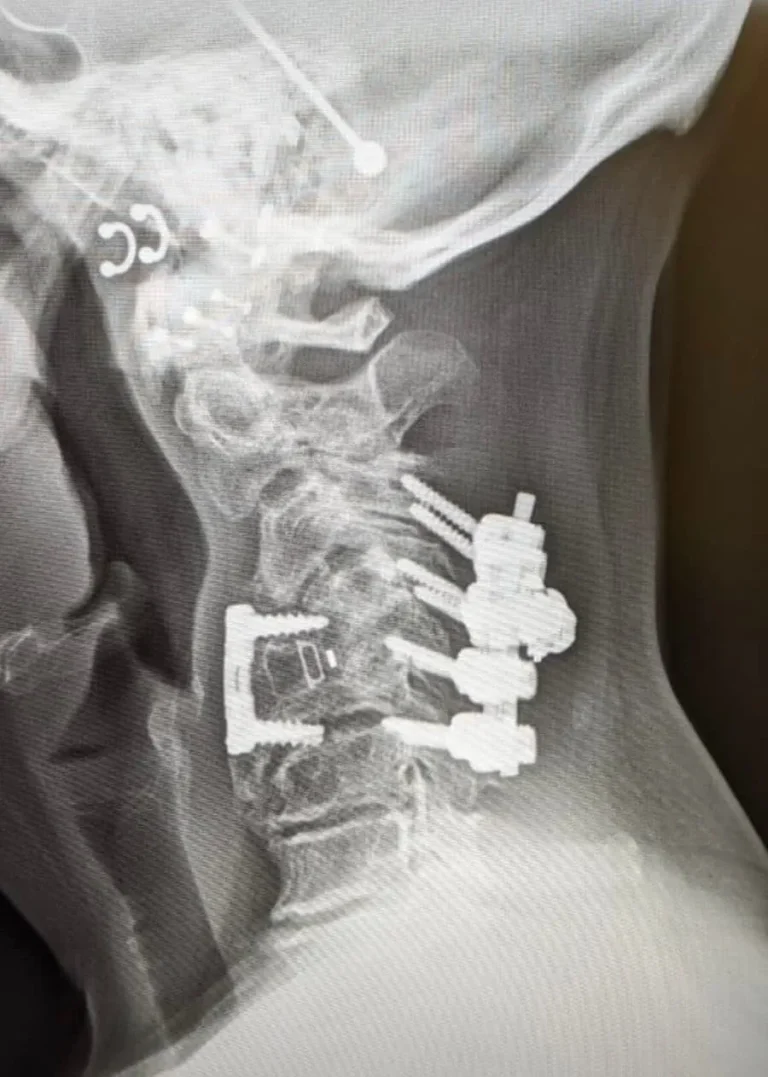

Fusion Frequently Needed

X-ray of a spine with surgical rods and screws implanted along the vertebrae.

90%+ Need Additional Surgery

Failed Discectomy to Fusion Pipeline

When multiple discectomies fail or the disc collapses, surgeons recommend fusion as the 'definitive solution.' Discectomy to repeat discectomy to fusion represents a predictable revenue stream, plus epidural scar tissue creates chronic pain requiring lifelong pain management.